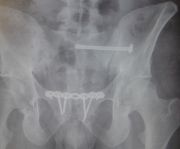

3. Pelvic fracture called also open book fracture in a 27-year-old male.

Treatment: Open reduction internal fixation of pubic symphysis and percutaneous fixation of the left sacroiliac joint

I. Before surgery II. Post-surgery, anteroposterior x-ray of pelvis showing one plate and six screws in pubic symphysis and one large screw in the left sacroiliac joint